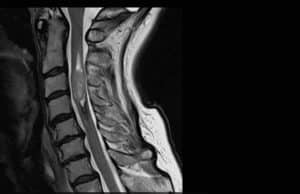

סרטן אינו תמיד מלווה בכאב או בסימנים דלקתיים ברורים. עם זאת, בעמוד השדרה המצב שונה: גידול הלוחץ על חוט השדרה או על שורשי העצבים גורם לכאב ולעיתים גם להפרעות נוירולוגיות.

הגידולים השכיחים ביותר הם אסטרוציטומה (astrocytoma) ואפנדימומה (ependymoma). גידולים אלה הם בתוך החומר של חוט השדרה. סרטן אחר כמו סרקומה מתפתח מהעצמות עצמן. מכאן שסרטן יכול להופיע מאחורי חוליות עמוד השדרה, בתוך עצבי חוט השדרה או במעטפת חוט השדרה. מבין הגידולים האלימים: כורדומה, וסרקומת יואינג.